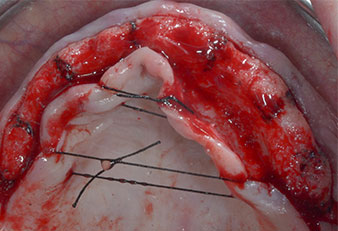

Fig. 1: Vista preoperatoria del borde maxilar, con las posiciones del implante marcadas con la ayuda de una plantilla quirúrgica de plástico. Debido a la baja altura del borde, se planificaron implantes posteriores supercortos.

Fig. 2: Después de la incisión en la zona crestal media y de la preparación de colgajos mucoperiósticos, las posiciones del implante se transfirieron al hueso.